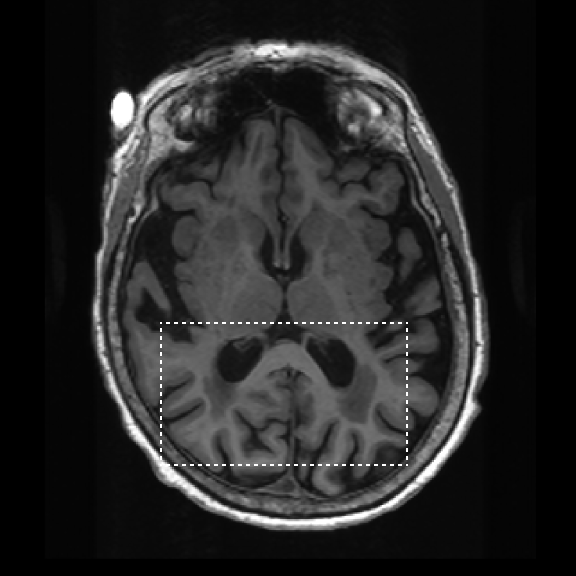

Retrospective brain volumetric analysis in a female patient diagnosed with Alzheimer’s disease at age 77 showed progressive brain atrophy over a 5-year period. The scans demonstrate temporal cortical atrophy with marked ex-vacuo enlargement of the lateral ventricles.

Temporal cortex

Hippocampus

Lateral ventricle